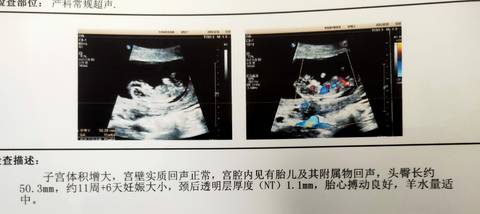

听别人说看nt能看出男女,有会看的吗